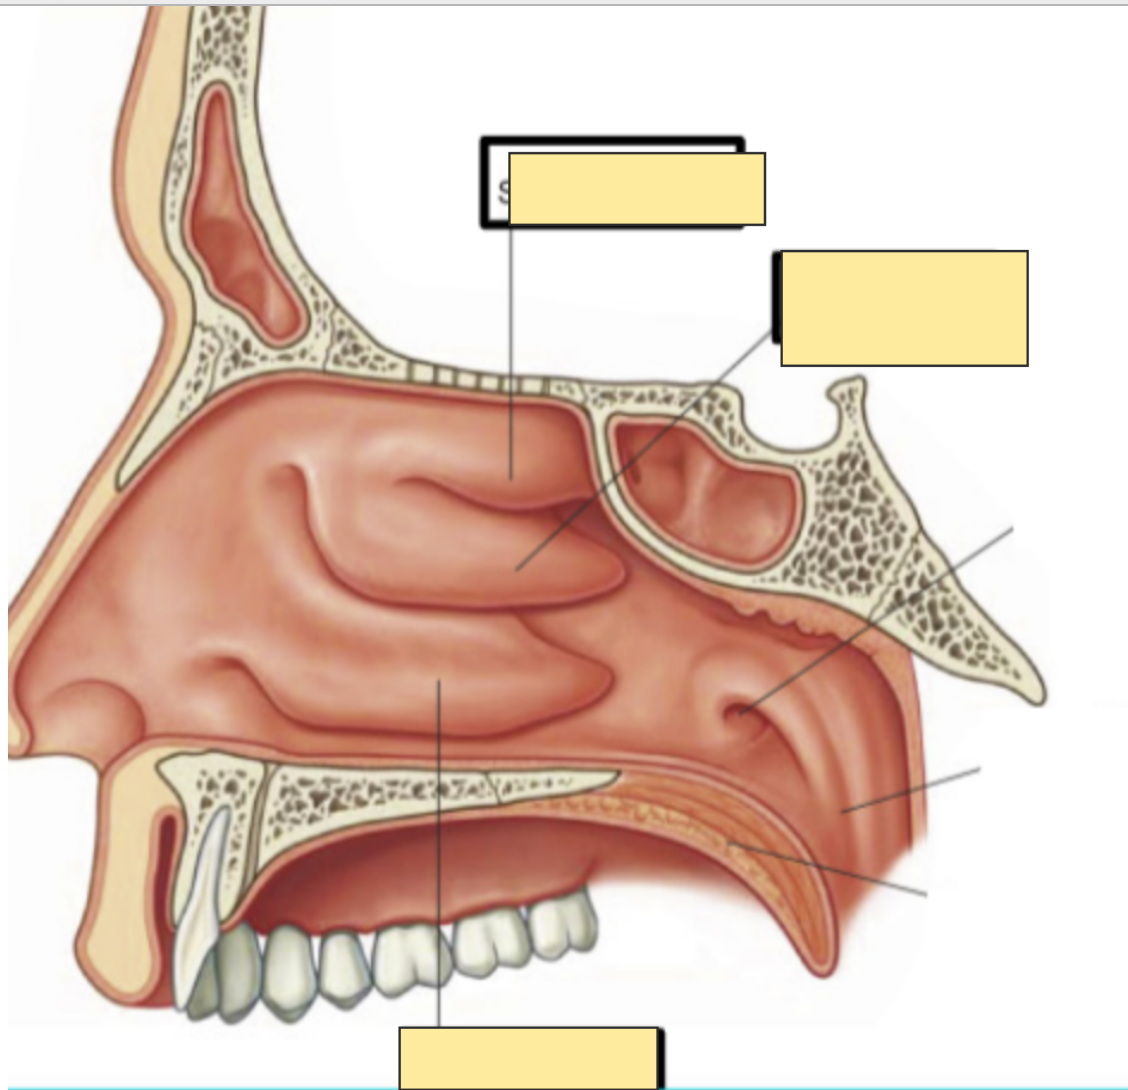

Q

label this saggital section of the medial wall of nasal cavity

A